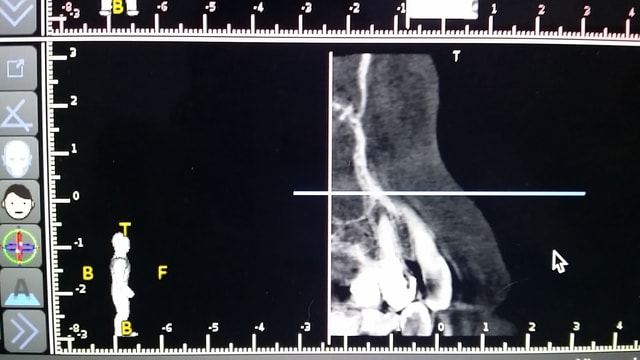

Bonjour à tous, que pensez vous d'une EII sur cette dent avec éventuellement mise en provisoire immédiate. La patiente ne veut pas d'appareil, et ne souhaite surtout pas rester sans dent... J'ai découvert cette PAA fortuitement à la rétro alvéolaire puis confirmée au CBCT. Pas de douleur particulière, dent ayant une clavette au passage.

Je partais sur un diamètre 4.2 à la base, avec forage à 3.7...Mais ça va être un peu trop chaud je pense. pas d'ancrage en apical comme l'a souligné Pluton

5 paa0 sagittal view lhrm1b - Eugenol